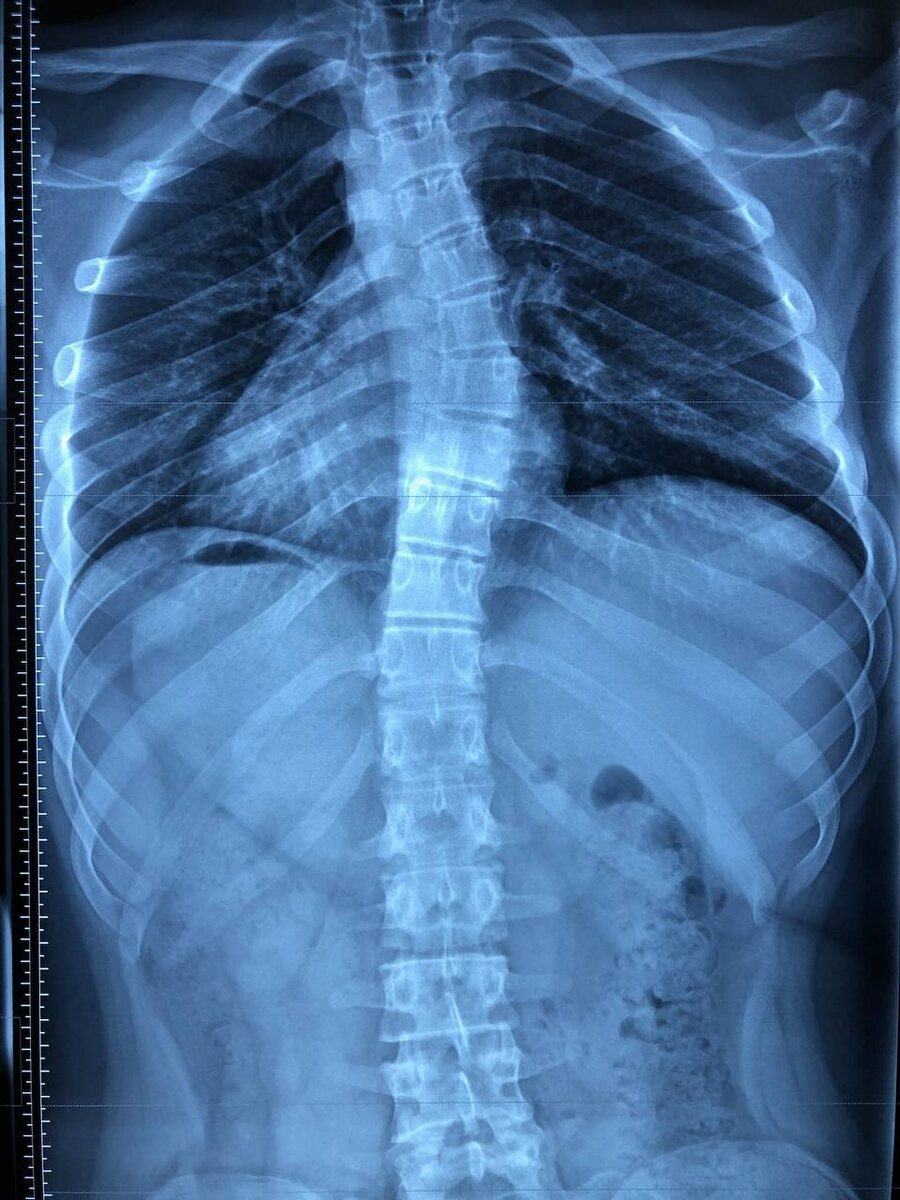

πŸ“Έ Π Π΅Π½Ρ‚Π³Π΅Π½ ΠΏΠΎΠ·Π²ΠΎΠ½ΠΎΡ‡Π½ΠΈΠΊΠ°: "Π·ΠΎΠ»ΠΎΡ‚ΠΎΠΉ стандарт" Π² диагностикС сколиоза

• ΠŸΠΎΠΊΠ°Π·Ρ‹Π²Π°Π΅Ρ‚ ΡƒΠ³ΠΎΠ» искривлСния ΠΏΠΎ ΠΌΠ΅Ρ‚ΠΎΠ΄Ρƒ Кобба β€” Π³Π»Π°Π²Π½Ρ‹ΠΉ ΠΊΡ€ΠΈΡ‚Π΅Ρ€ΠΈΠΉ для постановки Π΄ΠΈΠ°Π³Π½ΠΎΠ·Π°.

• Π’ΠΈΠ΄Π½Π° структура ΠΏΠΎΠ·Π²ΠΎΠ½ΠΊΠΎΠ², ΠΌΠ΅ΠΆΠΏΠΎΠ·Π²ΠΎΠ½ΠΎΡ‡Π½Ρ‹Ρ… дисков, Ρ‚Π°Π·Π°, Π³Ρ€ΡƒΠ΄Π½ΠΎΠΉ ΠΊΠ»Π΅Ρ‚ΠΊΠΈ.

πŸ“ Π’ Π’ΠΎΡ€ΠΎΠ½Π΅ΠΆΠ΅ Ρ€Π΅Π½Ρ‚Π³Π΅Π½ ΠΏΠΎΠ·Π²ΠΎΠ½ΠΎΡ‡Π½ΠΈΠΊΠ° ΠΌΠΎΠΆΠ½ΠΎ ΡΠ΄Π΅Π»Π°Ρ‚ΡŒ Π²ΠΎ ΠΌΠ½ΠΎΠ³ΠΈΡ… диагностичСских Ρ†Π΅Π½Ρ‚Ρ€Π°Ρ…, Π½ΠΎ Π²Π°ΠΆΠ½ΠΎ, Ρ‡Ρ‚ΠΎΠ±Ρ‹ снимок Π±Ρ‹Π» Π² ΠΏΠΎΠ»ΠΎΠΆΠ΅Π½ΠΈΠΈ стоя ΠΈ Π½Π° всю Π΄Π»ΠΈΠ½Ρƒ ΠΏΠΎΠ·Π²ΠΎΠ½ΠΎΡ‡Π½ΠΈΠΊΠ° (Π° Π½Π΅ Ρ‚ΠΎΠ»ΡŒΠΊΠΎ Π³Ρ€ΡƒΠ΄Π½ΠΎΠΉ ΠΈΠ»ΠΈ поясничный ΠΎΡ‚Π΄Π΅Π»).